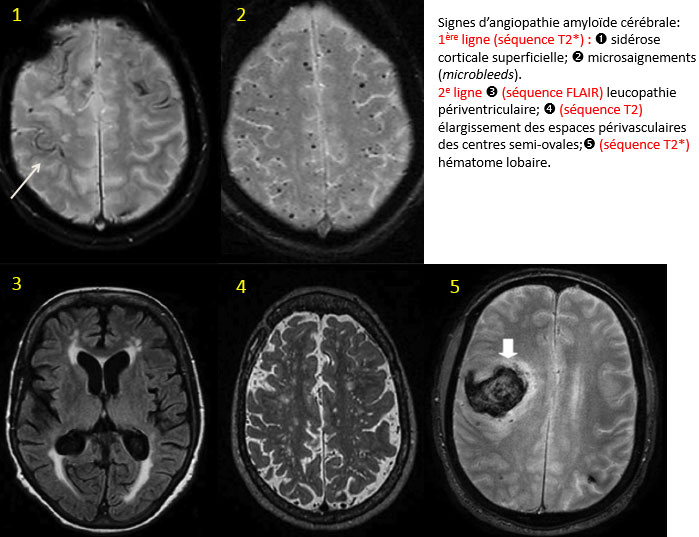

Un peu de neuf dans les angiopathies amyloïdes cérébrales

Dr Francois Sellal CMRR de Strasbourg-Colmar - Colmar

L'angiopathie amyloïde cérébrale (AAC) est une maladie touchant principalement les petites artères corticales et les artères lepto-méningées, due au dépôt de protéine Aβ dans leurs parois. Elle touche surtout les sujets âgés et peut se caractériser soit par des hémorragies lobaires majeures, soit par un déclin cognitif rapide avec événements neurologiques transitoires (souvent attribués à des microsaignements). Enfin, l'angiopathie amyloïde est présente, quoique relativement légère, dans la maladie d'Alzheimer.